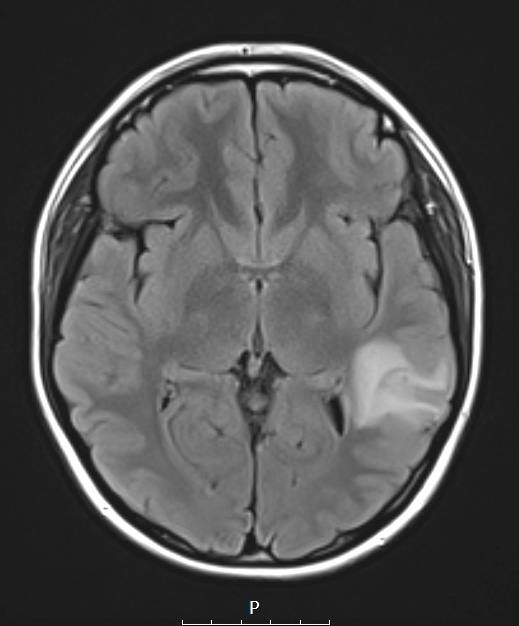

Washington University Experience | NEOPLASMS (NEURONAL) | Ganglioglioma | 23A1 Ganglioglioma (Case 23) T2 FLAIR 2

Case 23 History ---- The patient is a 21yo female with a history of a low-grade glioneuronal neoplasm discovered at an outside hospital after presenting with new-onset seizures. ---- 23A1-4 ---- 23A1 There is a hyperintense signal on this FLAIR examination.